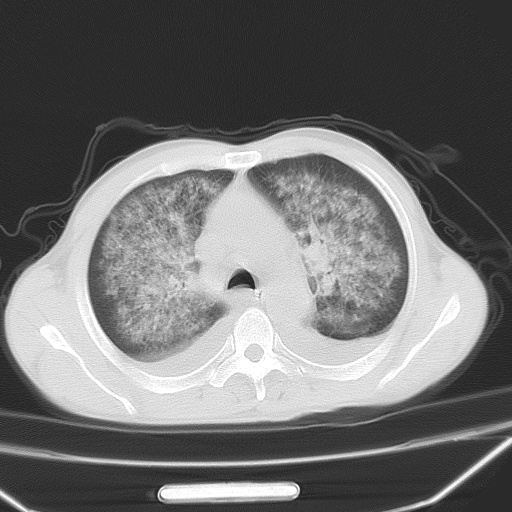

男、42岁、咯血3天。既往有甲亢、贫血、血尿蛋白尿史多年。血象:wbc:6.   中性粒:70.6%。

双肺野对称性磨玻璃影,分布于内中带,双侧胸水,患者有咯血。

双肺野广泛对称性磨玻璃影、实变影,以肺门为中心,主要分布于内中带,符合典型肺泡性肺水肿;伴双侧胸腔少量游离积液。结合患者既往病史且咯血就诊,支持多因素(尿毒症等)所致之肺水肿、肺出血、胸水;影像表现暂不考虑心源性水肿,且症状也不太符。需密切随诊结合临床治疗等进一步明确。

心影增大密度略低,双肺磨玻璃样高密度影及双侧胸腔积液,考虑心功能不全继发双肺肺水肿及双侧胸腔积液。心影密度略低,考虑贫血所致。